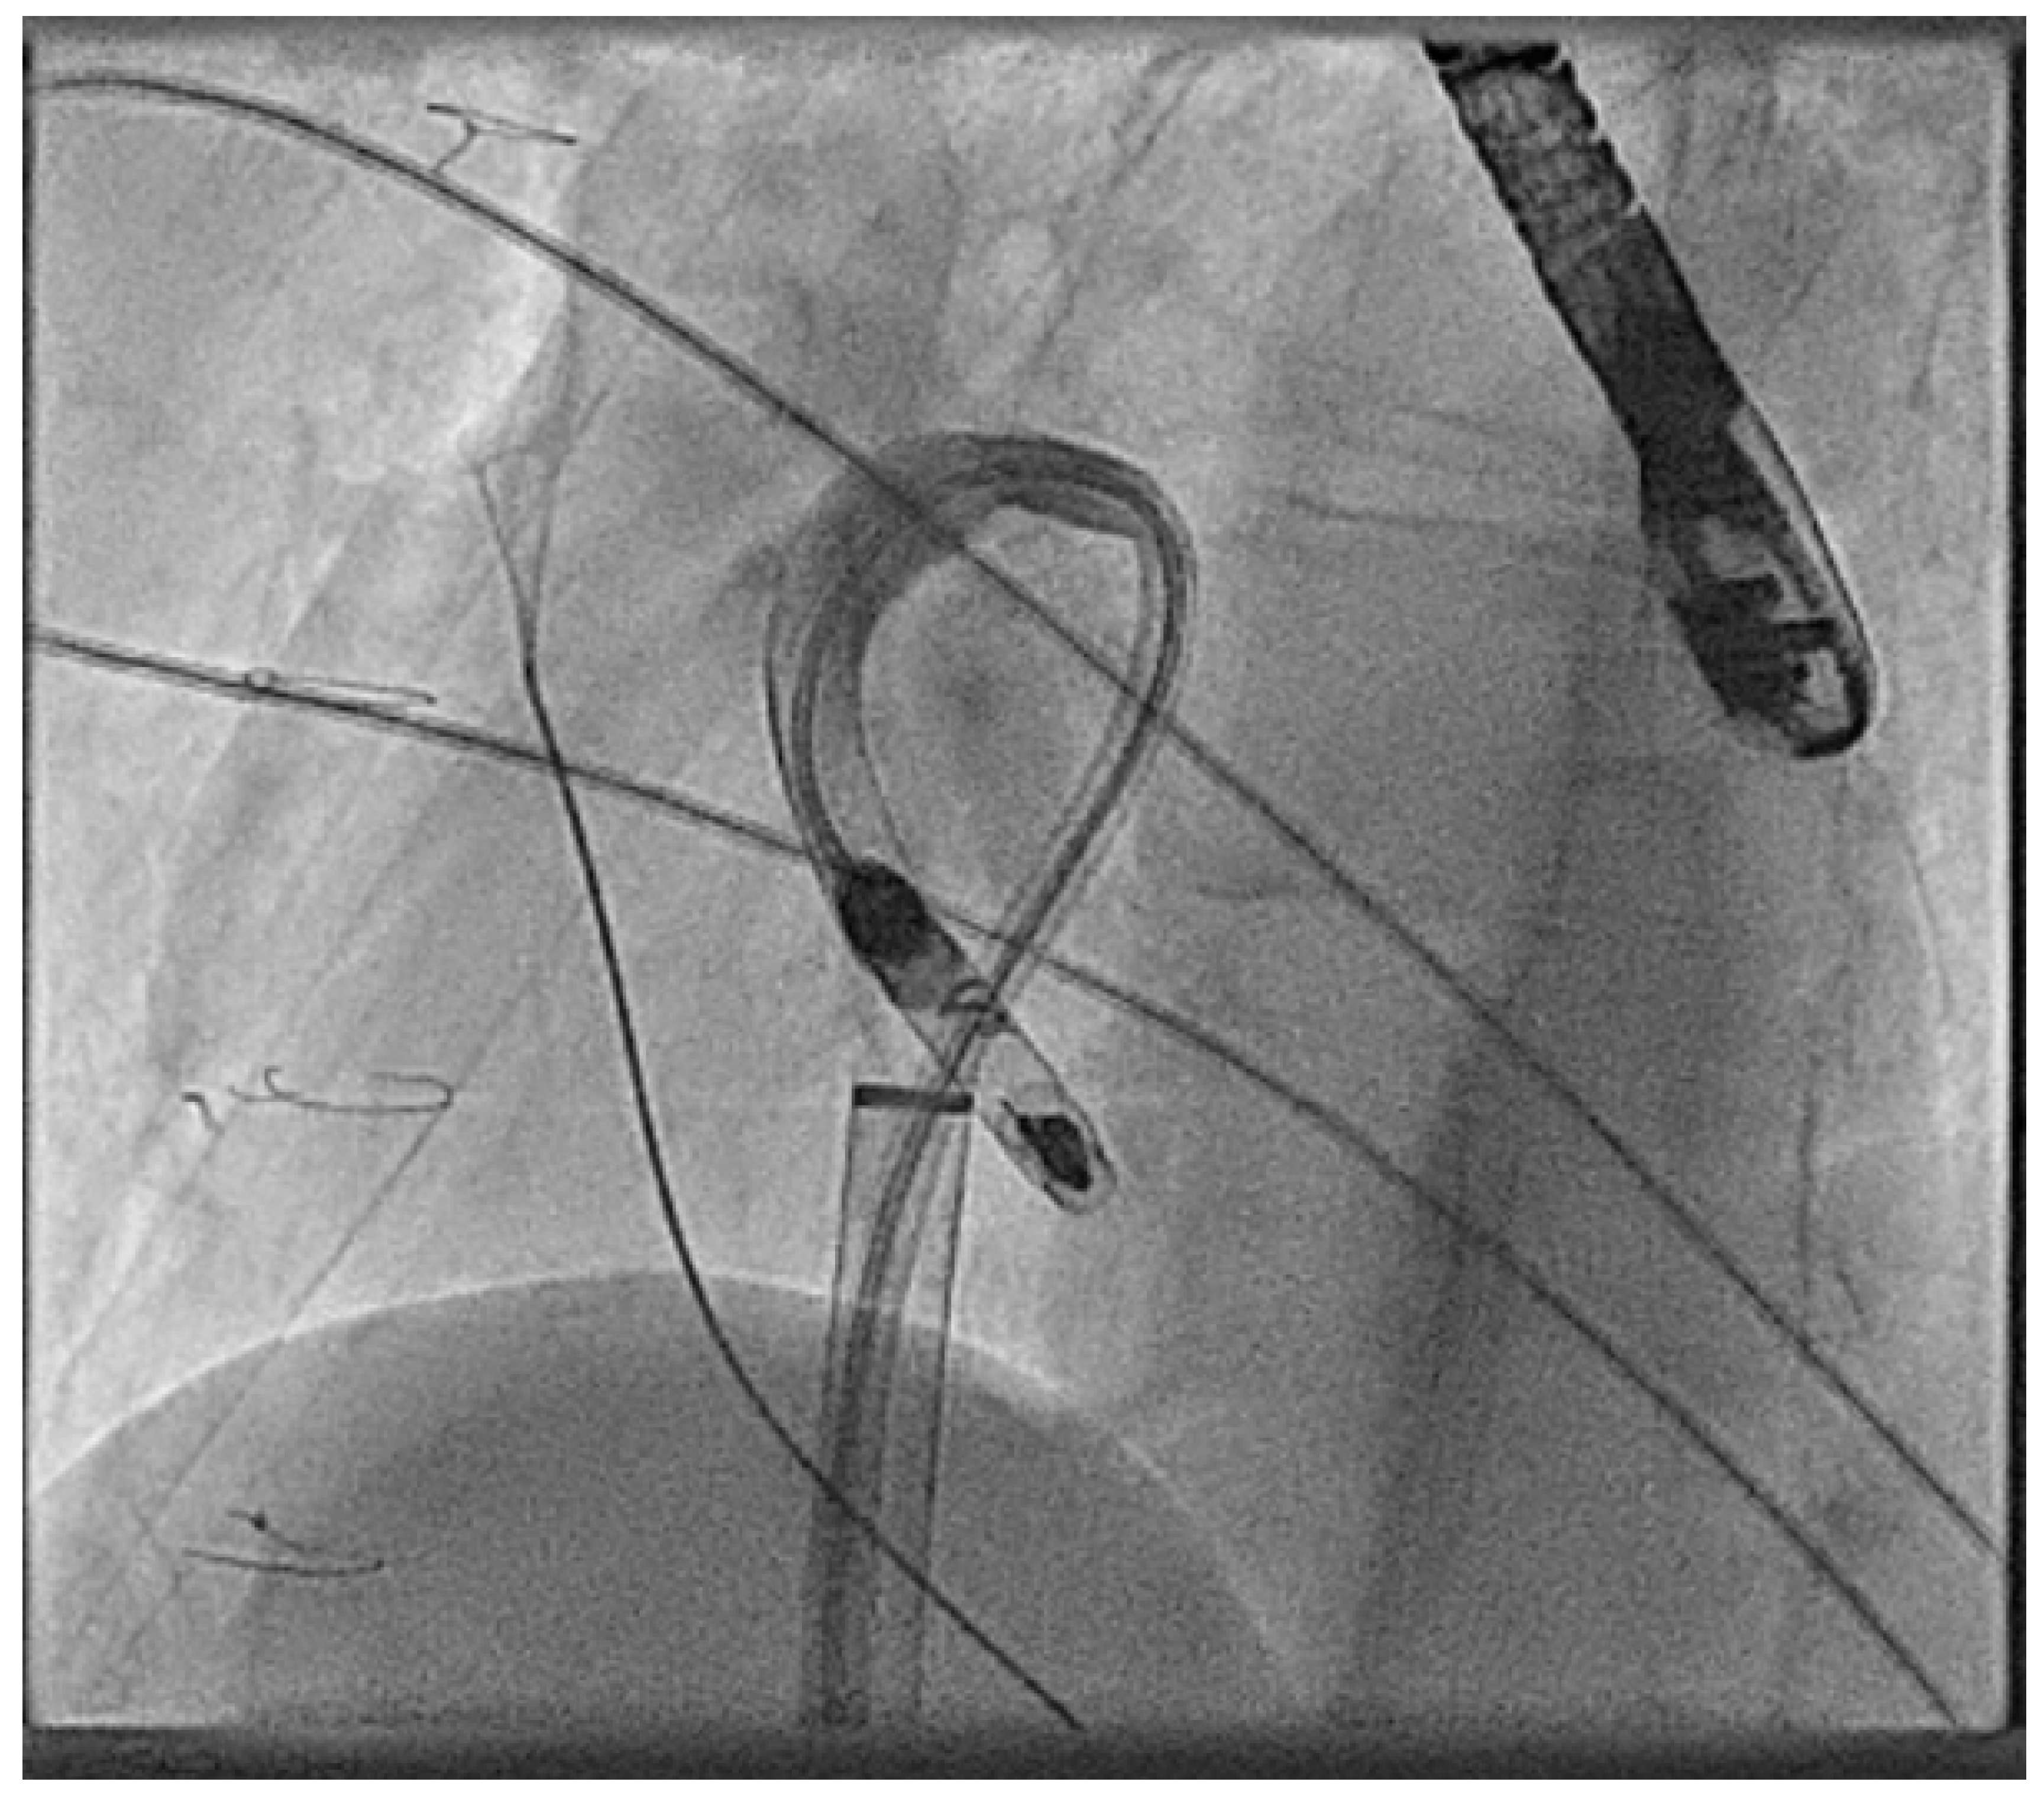

- Calvert, P.; Yeo, C.; Rao, A.; Neequaye, S.; Mayhew, D.; Ashrafi, R. Transcarotid implantation of a leadless pacemaker in a patient with Fontan circulation. Hear. Case Rep. 2023, 9, 53–58. [Google Scholar] [CrossRef]

- Hayle, P.; Altayeb, F.; Hale, A.; Rao, A.; Ashrafi, R. Case report demonstrating novel approaches for leadless pacemaker implantation in the single ventricle heart. Eur. Heart J. Case Rep. 2025, 9, ytaf146. [Google Scholar] [CrossRef]

- Goulden, C.J.; Khanra, D.; Llewellyn, J.; Rao, A.; Evans, A.; Ashrafi, R. Novel approaches for leadless pacemaker implantation in the extra-cardiac Fontan cohort: Options to avoid leaded systems or epicardial pacing. J. Cardiovasc. Electrophysiol. 2023, 34, 2386–2392. [Google Scholar] [CrossRef]